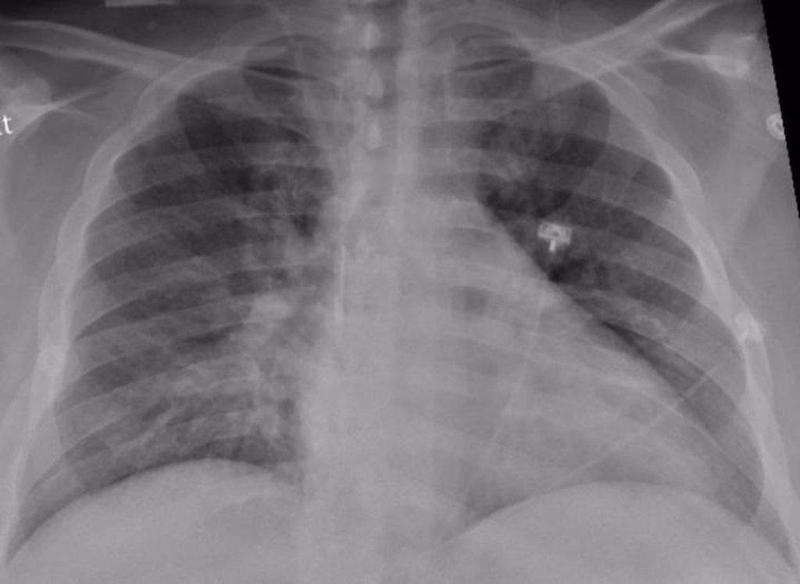

Un nuevo estudio del Colegio de Médicos y Cirujanos Vagelos de la Universidad de Columbia y del Centro Oncológico Integral Herbert Irving (Estados Unidos) ha dibujado la imagen más detallada hasta ahora de la infección por SARS-CoV-2 en el pulmón, revelando los mecanismos que dan lugar a la COVID-19 letal, y puede explicar las complicaciones a largo plazo y mostrar cómo la COVID-19 difiere de otras enfermedades infecciosas.

Publicado en la revista 'Nature', el estudio descubrió que, en los pacientes que murieron a causa de la infección, la COVID-19 desencadenó una trifecta perjudicial de inflamación desbocada, destrucción directa y regeneración alterada de las células pulmonares que intervienen en el intercambio de gases, y cicatrización pulmonar acelerada.

Este nuevo estudio es único con respecto a otras investigaciones, ya que examina directamente el tejido pulmonar (en lugar de esputo o lavados bronquiales) utilizando perfiles moleculares unicelulares que pueden identificar cada célula en una muestra de tejido y registrar la actividad de cada célula, lo que da lugar a un atlas de células en el pulmón tras la COVID-19.